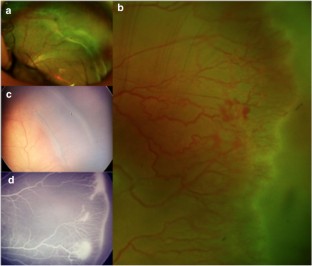

Retrospective chart review of all patients diagnosed with ROP1 initially treated with IVB in 6 tertiary referral centers of Toluca and Mexico City from 2005 to 2017. Treatment failure was defined as persistence or progression of neovascularization, elevation of the ridge, worsening of plus disease, or retinal crunch within the first week after treatment. Recurrence was defined as the new appearance of plus disease, an elevated ridge, or pathological new vessels after an initial regression of ROP following treatment. Therapy was observation, switch of anti-VEGF agent, retinal photocoagulation, vitrectomy, or a combination of two or more, depending on the severity of findings.

A total of 672 patients who received intravitreal bevacizumab injection for ROP1 treatment were included. Of these, 2.5% (17 patients) failed to treatment, 6.8% (46 patients) developed a recurrence for ROP, and 5.5% (37 patients) carried a misdiagnosis of recurrence and were diagnosed with other than ROP1 after examination. Based on the severity of findings, patients with recurrence or treatment failure were further treated by observation, repeat anti-VEGF intravitreal injection (bevacizumab or other), laser photocoagulation, vitrectomy, or a combination of these. Based on the treatment results, a therapeutic algorithm was created.